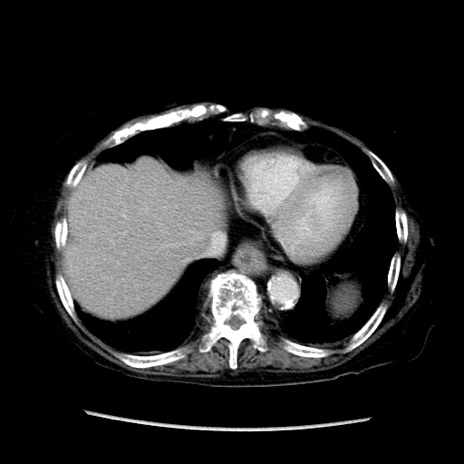

症例14(横断像)

【症例】 90歳代女性

【主訴】 腹痛・嘔吐

【現病歴】今朝から左側腹部痛を認めた。 経過観察していたが、嘔吐を認めたため来院。

【既往歴】 子宮癌術後

【身体所見】 意識清明、BP 127/54mmHg、P 98bpm Sp02 95%(RA)、BT 35.8°C、腹部平坦・軟腸ぜん動音聴取良好、右下腹部圧痛(+) 反跳痛なし

【データ】WBC 9800、CRP 0.46